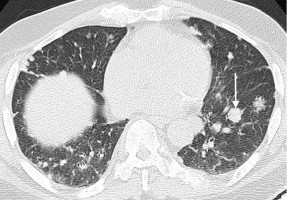

In terms of patient selection, workgroup members agreed that PSMA PET should be performed within three months of treatment or since progression on the last therapy to ensure that the current disease state is represented.

Either 18F-DCFPyL or 68Ga-PSMA-11 can be used for PSMA PET imaging, and 18F-FDG PET is not required as a standard patient selection tool.

In addition, patients should be imaged with either contrast-enhanced CT or MRI to identify potential PSMA-negative disease.